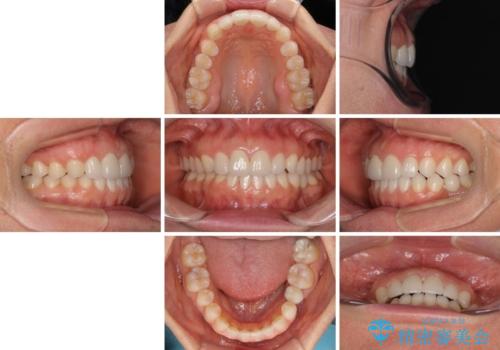

- 大きすぎる上顎前歯と、隙間の空いた下顎歯列を気にして来院された患者様です。

上顎前歯にはセラミッククラウンが装着されており、顔や他の歯と比較して幅の大きい状態でした。

下顎前歯は空隙歯列弓であったので、アンカースクリューとワイヤー装置を用いてスペースを閉じていくこととし、上顎前歯は矯正治療用の仮歯に置き換えた上で、仮歯の大きさを削って小さくしながら、上下前歯部の部分矯正を行うこととしました。

矯正治療後は、仮歯とした上顎前歯をオールセラミッククラウンにて補綴治療を行うこととしました。

日本と海外を拠点に仕事をされていらっしゃるため、数ヶ月治療があいてしまうことがあり、期間はかかりましたが、2年間で望み通りの前歯に仕上げることができました。